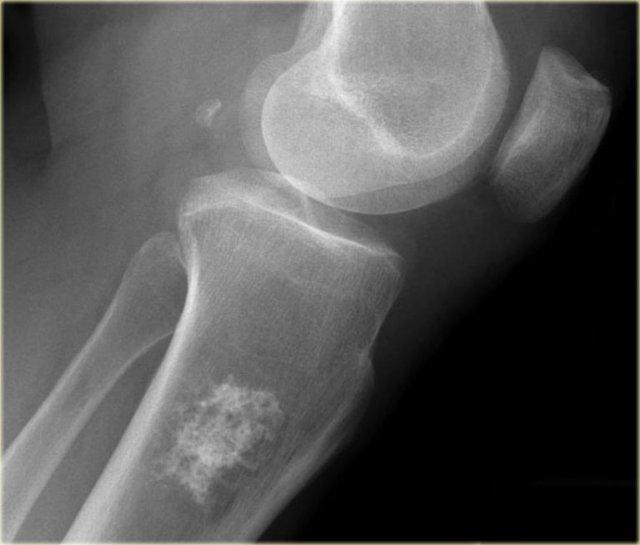

Hình ảnh cho thấy một tổn thương vôi hóa ở đầu gần xương chày mà không có đặc điểm đáng ngờ.

Đây rất có thể là một u sụn nội xương (enchondroma).

Có những đặc điểm khác ủng hộ chẩn đoán sarcoma sụn độ thấp như xạ hình xương dương tính và hình ảnh xói mòn nội màng xương trên MRI (không hiển thị).

Sarcoma sụn đã được chẩn đoán qua sinh thiết.